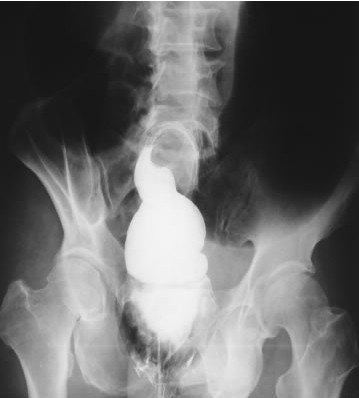

照片名称:静脉尿路造影